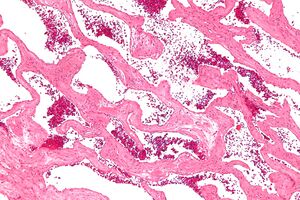

Micrograph of a cavernous liver hemangioma. H&E stain. | |

Gradient-echo T2WI magnetic resonance imaging (MRI) is most sensitive method for diagnosing cavernous hemangiomas.[21] MRI is such a powerful tool for diagnosis, it has led to an increase in diagnosis of cavernous hemangiomas since the technology's advent in the 1980s.[16] The radiographic appearance is most commonly described as "popcorn" or "mulberry"-shaped.[22] Computed tomography (CT) scanning is not a sensitive or specific method for diagnosing cavernous hemangiomas.[23] Angiography is typically not necessary, unless it is required to rule out other diagnoses. Additionally, biopsies can be obtained from tumor tissue for examination under a microscope. It is essential to diagnose cavernous hemangioma because treatments for these lesions are less aggressive than that of cancerous tumors, such as angiosarcoma. However, since MRI appearance is practically pathognomonic, biopsy is rarely needed for verification.[23]